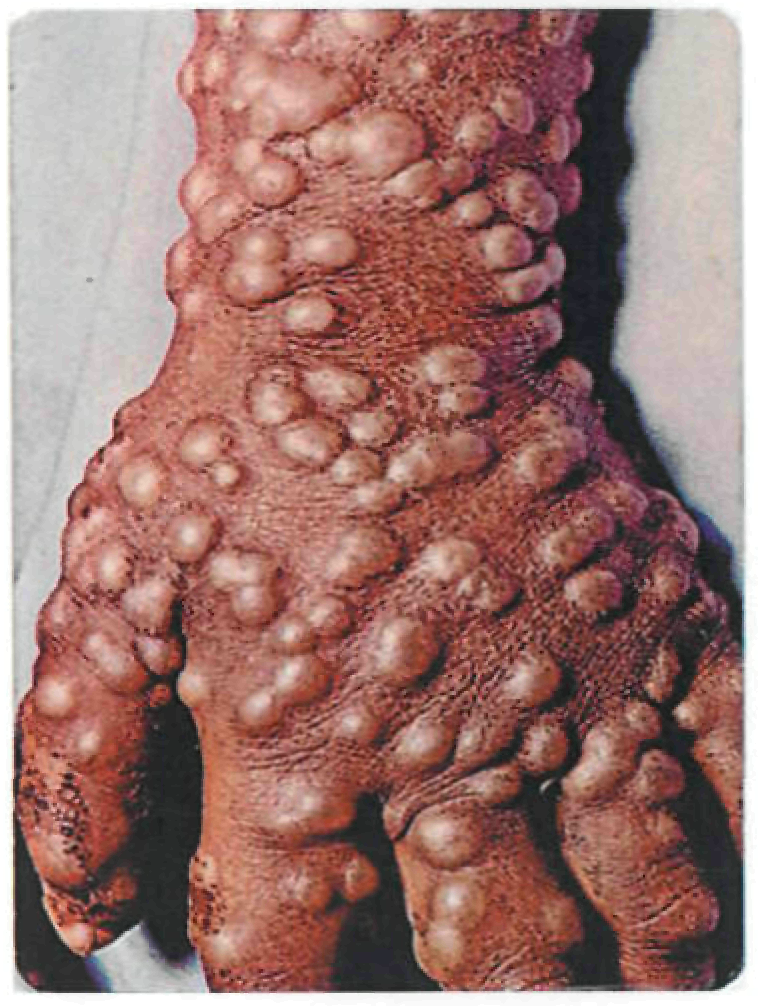

В 95% случаев сыпь поражает лицо, в 75% - ладони и подошвы, что является отличительным признаком заболевания. Также поражаются слизистые оболочки полости рта (в 70% случаев), половые органы (30%), конъюнктива и/или роговица (20%). У части пациентов имеет место проктит с поражениями перианальной области изолированно или в сочетании с высыпаниями в области гениталий [39]. Количество элементов сыпи варьирует от единичных до нескольких тысяч [13].

При формировании пустул вновь повышается температура тела, нередко до 39-40°С, состояние больных значительно ухудшается, развиваются тахикардия, артериальная гипотензия, одышка, сильный зуд кожи. Возможны диарея, лимфаденит (чаще шейный и паховый).